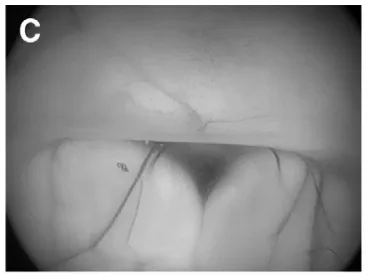

采用先行神经内镜第三脑室造瘘(B-F内镜下视野),再行开颅肿瘤切除的方案,具体过程如下:

(C)第三脑室底,可见乳头体结构